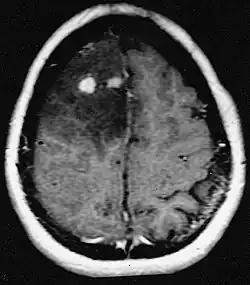

Mozkové metastázy jsou nejčastějšími intrakraniálními novotvary u dospělých, jsou desetkrát častější než primární mozkové nádory. Krokují na 20 do 40 procenta dospělých s rakovinou a jsou spojeny hlavně s rakovinou plic a prsu a melanomem. Tyto léze jsou výsledkem šíření rakovinných buněk krevním řečištěm a nejčastěji se vyskytují na křižovatce šedé a bílé hmoty, kde se mění průřez krevních cév a zachycují embolie nádorových buněk. 80 procento lézí se vyskytuje v mozkových hemisférách, 15 procenta v mozečku a 5 procent v mozkovém kmeni. Asi 80 procento pacientů má v anamnéze systémovou rakovinu a 70 procento má četné mozkové metastázy.

V diagnostice a léčbě těchto lézí bylo nedávno dosaženo významného pokroku, jehož výsledkem je lepší přežití a kontrola symptomů. Nástup známek a symptomů je podobný jako u jiných masivních lézí v mozku. Diagnostickou metodou volby je magnetická rezonance s použitím kontrastních látek.

Literatura uvádí ekvivalentní výsledky pro chirurgii a radiochirurgii. Posledně jmenované se jeví jako pohodlnější, účinnější a bezpečnější pro malé léze nebo v oblastech nepřístupných pro chirurgii. Radiochirurgie je rozumnou alternativou pro pacienty, kteří nemohou být ze zdravotních důvodů operováni. Chirurgie je však jednoznačně optimální metodou k získání tkání pro diagnostiku a odstranění lézí, které způsobují masový efekt. Radiochirurgie a chirurgie by proto měly být lépe považovány za dvě komplementární, ale odlišné metody, které je třeba aplikovat v závislosti na různé situaci pacienta. Za skoro 50 procento pacientů s jednou nebo dvěma mozkovými metastázami není kandidáty na chirurgické odstranění kvůli nepřístupnosti lézí, rozsahu systémového onemocnění nebo jiným faktorům. Těmto a dalším pacientům s mnohočetnými metastázami je obvykle nabízena panencefalická radiační terapie jako standardní péče. Ve skutečnosti dosahují až téměř 50 procent z nich touto terapií zlepšení neurologických příznaků a 50 do 70 procent znatelná reakce. Chemoterapie se zřídka používá především u mozkových metastáz.